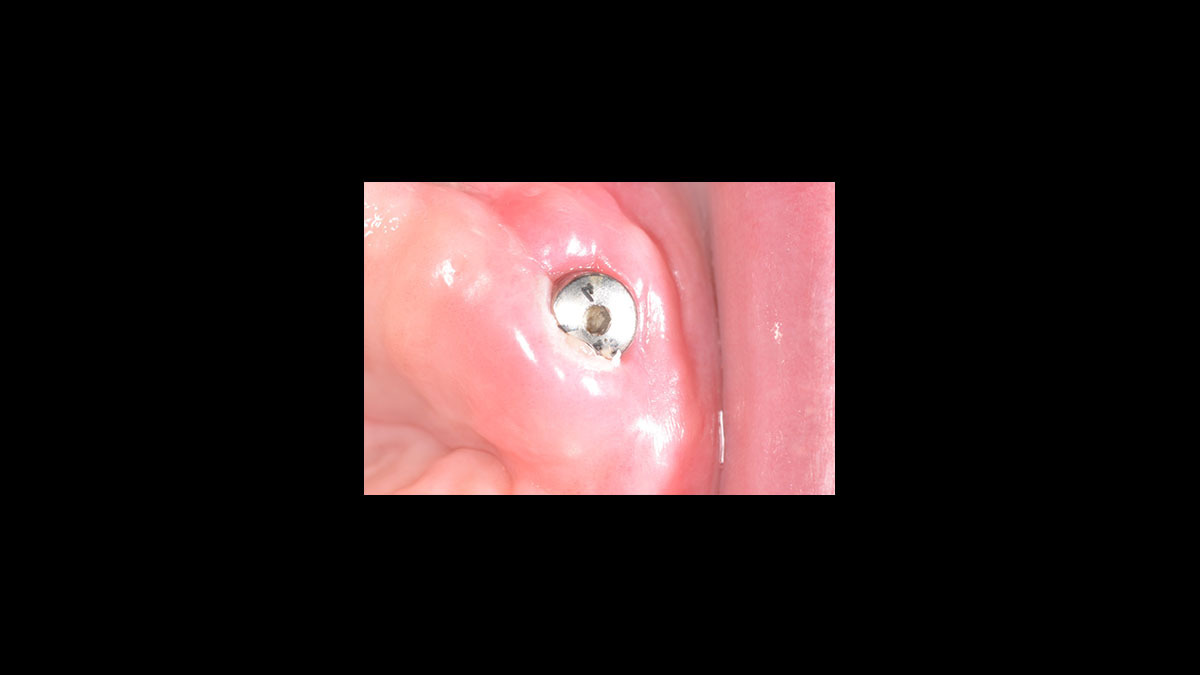

Descubrimiento del implante